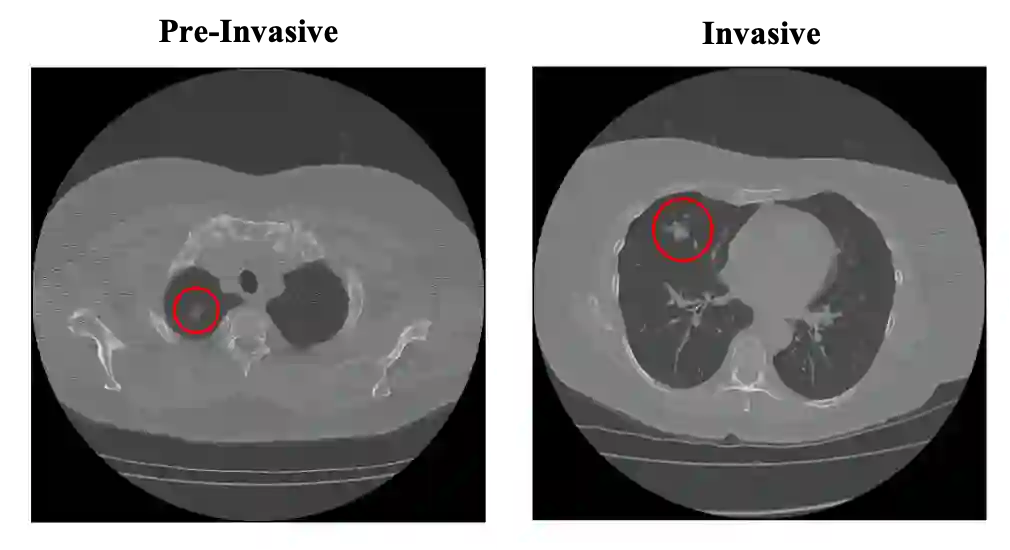

Lung cancer is the leading cause of mortality from cancer worldwide and has various histologic types, among which Lung Adenocarcinoma (LUAC) has recently been the most prevalent. Lung adenocarcinomas are classified as pre invasive, minimally invasive, and invasive adenocarcinomas. Timely and accurate knowledge of the invasiveness of lung nodules leads to a proper treatment plan and reduces the risk of unnecessary or late surgeries. Currently, the primary imaging modality to assess and predict the invasiveness of LUACs is the chest CT. The results based on CT images, however, are subjective and suffer from a low accuracy compared to the ground truth pathological reviews provided after surgical resections. In this paper, a predictive transformer-based framework, referred to as the "CAE-Transformer", is developed to classify LUACs. The CAE-Transformer utilizes a Convolutional Auto-Encoder (CAE) to automatically extract informative features from CT slices, which are then fed to a modified transformer model to capture global inter-slice relations. Experimental results on our in-house dataset of 114 pathologically proven Sub Solid Nodules (SSNs) demonstrate the superiority of the CAE-Transformer over the histogram/radiomics-based models and its deep learning-based counterparts, achieving an accuracy of 87.73%, sensitivity of 88.67%, specificity of 86.33%, and AUC of 0.913, using a 10-fold cross-validation.